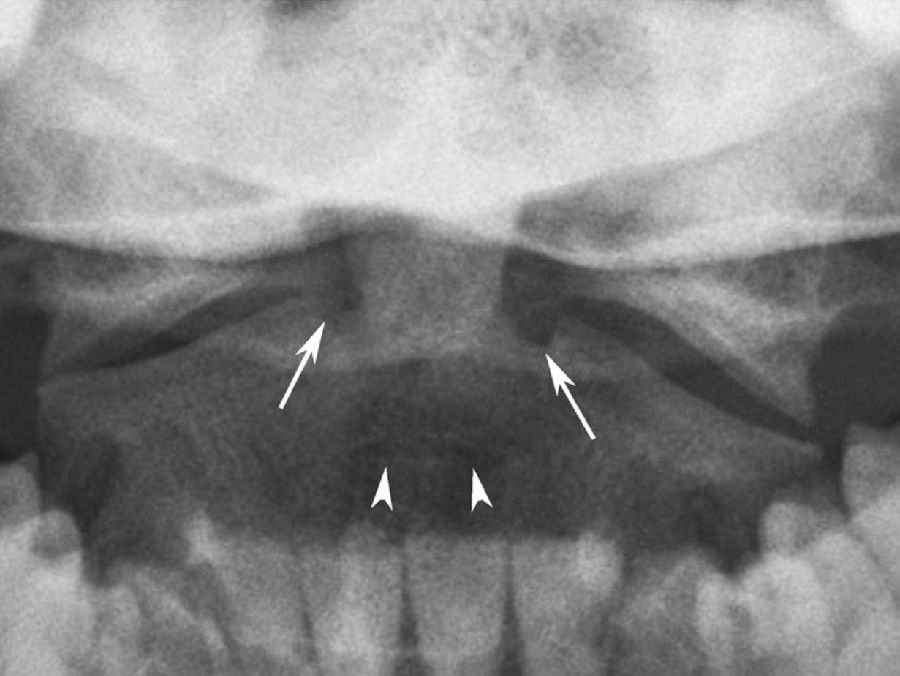

图3 枢椎上关节面内侧切迹和软骨盘

枢椎上关节面内侧可见裂隙状切迹(箭),为齿突和枢椎椎体骨化中心与先前的软骨区融合后的痕迹;齿突与枢椎体间的软骨盘可存留至成年,常有硬化边(箭头)。

齿突尖通常呈半球形,亦可为圆锥形,或呈逐渐变细的尖头状。齿突本身可呈尖爪形或球形,或明显细长超出寰椎前弓。齿突尖内偶可见局限性密度增高区,为终末小骨融于齿突所致。先天性齿突不连表现为齿突尖端和其下部分离,类似于骨折,两者区别在于先天性齿突不连无明显创伤史,且分离处有光滑的硬化边。枢椎上关节面内侧可见不同程度的裂隙状切迹,偶可呈孔状,为齿突和枢椎椎体骨化中心与先前的软骨区融合后的痕迹(图3)。齿突与枢椎体间的软骨盘可存留至成年,常有硬化边或椎体前面切迹(图3)。